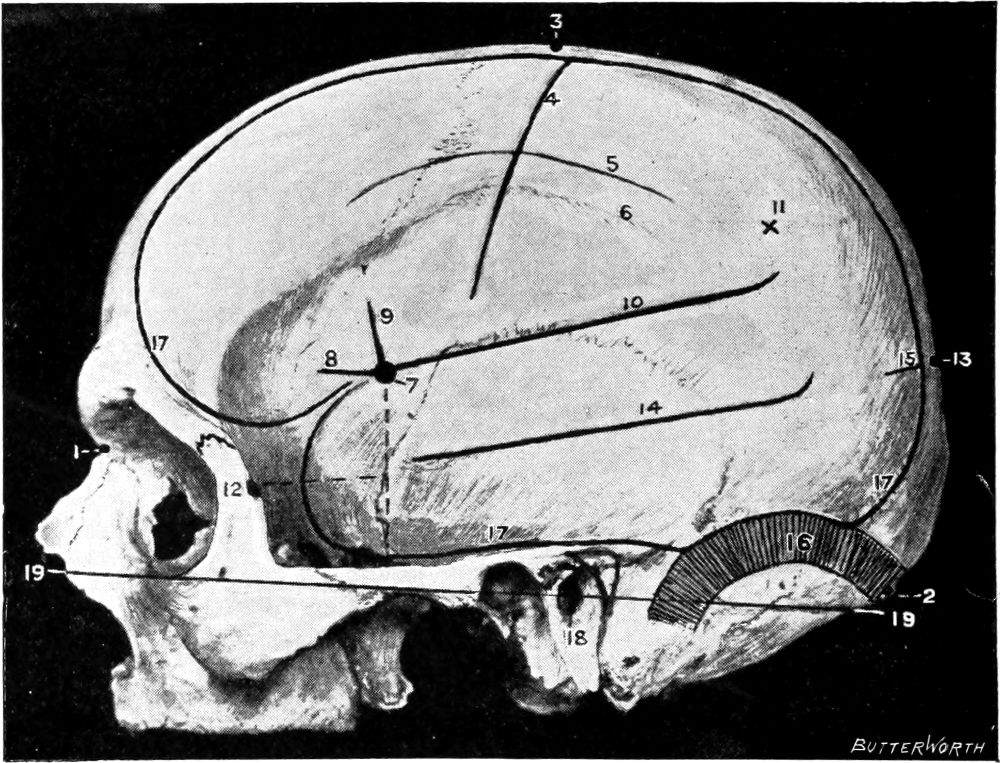

Fig. 1. Cranio-cerebral Topography. 1, The nasion; 2, The inion; 3, The mid-point between nasion and inion; 4, The Rolandic fissure; 5, The superior temporal crest; 6, The inferior temporal crest; 7, The Sylvian point; 8, The anterior horizontal limb of the Sylvian fissure; 9, The vertical limb of the Sylvian fissure; 10, The posterior horizontal limb of the Sylvian fissure; 11, The parietal prominence; 12, The malar tubercle; 13, The lambda; 14, The first temporo-sphenoidal sulcus; 15, The external parieto-occipital sulcus; 16, The lateral sinus; 17, 17, 17, The level of the base of the cerebrum; 18, The external auditory meatus; 19, 19, Reid’s base-line. (Reproduced, by the permission of Mr. H. K. Lewis, from the author’s work on ‘Landmarks and Surface-markings’.)

Fig. 2. Cranio-cerebral Topography. 1, 1, Reid’s base-line; 2, 2, A line parallel to the above at the level of the supra-orbital margin; 3, The middle meningeal artery; 4, The anterior branch; 5, 5, 5, The three sites for trephining; 6, The posterior branch; 7, The site for trephining; 8, The point for trephining to reach the descending horn of the lateral ventricle; 9, The lateral sinus; 10, The inion; 11, The mastoid process; 12, Macewen’s suprameatal triangle; 12a, The mastoid antrum; 12b, The facial nerve; 13, The suprameatal and supramastoid crests; 14, 14, The temporal crest; 15, The temporal fossa; 16, The external angular frontal process; 17, The tendo-oculi attachment; 18, The lachrymal groove. (Reproduced, by the permission of Mr. H. K. Lewis, from the author’s work on ‘Landmarks and Surface-markings’.)